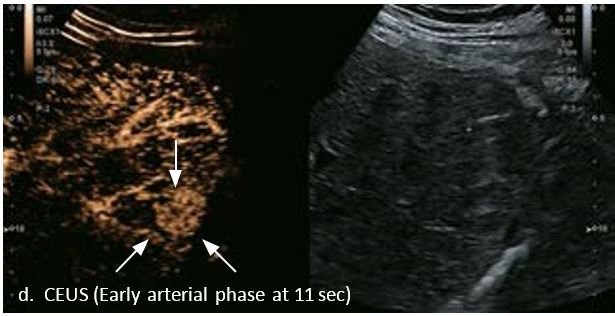

Оцінка результатів лікування ГЦК

Проведено повторне обстеження 79-річного чоловіка з цирозом печінки В, ускладненим ГЦК, після транс-артеріальної хіміоемболізації (ТАХЕ). Було виявлено нове ураження, розташоване поруч з ураженням після ТАХЕ. На сірошкальному зображенні чітко видно нове ураження, але складно виявити рецидив ГЦК в зоні ураження після ТАХЕ. За допомогою кольорового картування SMI (cSMI) можна побачити розвинену судинну мережу всередині нового вогнища ураження. Для оцінки результату лікування було виконано CEUS. За допомогою CEUS можна легко дослідити як нове ураження, так і рецидив ГЦК у вогнищі ураження після TACE. Нове ураження демонструє гіперпосилення артеріальної фази і відсутність вимивання до 5 хвилин, отже, це ураження LI-RADS 4, ймовірна ГЦК за критеріями LI-RADS. Підживлюючі судини можна чітко спостерігати в ранній артеріальній фазі. Для ураження після TACE, більша його частина не підсилюється, однак, в артеріальній фазі спостерігається ділянка гіперпосилення у верхній частині лікованого ураження, що вказує на рецидив ГЦК.

Малюнок 10